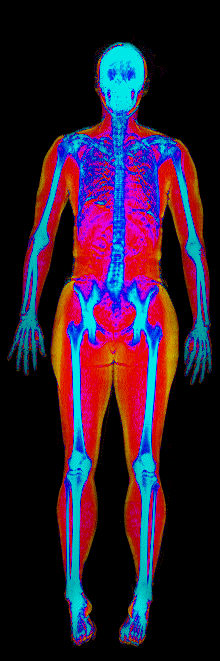

A DEXA scan passes two low-dose X-ray beams through your entire body, head to toe. Different tissues absorb different amounts of energy: bone absorbs the most, muscle and lean tissue less, and fat the least. The scanner reads how much energy made it through every pixel and assigns each one to a tissue type.

The colorful image at the top of every BodyStats DEXA report is literally that map. Bone shows up in cyan and white. Lean tissue is red. Fat is yellow and orange. Your body-fat percentage isn’t an inference — it’s a count of how much of that image is yellow and orange, broken out region by region: left arm vs right, left leg vs right, trunk, android (belly), gynoid (hips). And visceral fat — the dangerous abdominal fat that bioimpedance can’t see at all — comes back as its own number in cm².

This page features real, anonymized DEXA scan images from BodyStats clients, organized by gender and body fat percentage in 5% increments. DEXA (Dual-Energy X-ray Absorptiometry) is the clinical gold standard for measuring body composition — far more accurate than scales, calipers, or visual estimates.

Each colorized scan shows the distribution of fat tissue (shown in warmer colors) and lean tissue (cooler colors) throughout the body. Compare your own DEXA scan to others in your range, or see what different body fat levels actually look like on a scan.

Male DEXA Scans by Body Fat %

10 to 15% body fat